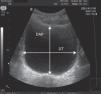

A los pacientes del grupo de estudio se les realizó una o varias ecografías abdominales con insonización transversal desde la región suprapúbica para determinar el mayor diámetro anteroposterior (DAP) y transversal (DT) de la vejiga, así como la dirección de los mismos (fig. 1). No se llevó a cabo la PSP hasta constatar un DAP vesical de al menos 1,5cm. Todos los procedimientos fueron realizados por el mismo investigador (S.B.) utilizando 2 ecógrafos, Esaote MyLab® 25 Gold o Hewlett Packard Sonos® 5500, según su disponibilidad, con sonda convexa de 3,5MHz. El porcentaje de éxito de la técnica al primer intento y total por paciente, número de PSP realizadas y el volumen total de orina obtenido se comparó con un grupo control de 50 pacientes de la misma edad y características clínicas, a quienes se realizó PSP sin guía ecográfica. En estos casos se colocó una bolsa de orina estéril para confirmar la ausencia de micción durante al menos 30min antes de realizar la PSP, manteniéndose hidratación oral o fluidoterapia i.v.

Se estudió la relación entre los diámetros (DAP y DT) y el volumen total de orina obtenido en las PSP ecoguiadas, encontrándose una buena correlación en ambos casos, aunque algo superior para el DAP (r=0,637, p<0,05). La figura 2 muestra la distribución de datos junto con la recta de regresión y los intervalos de confianza al 95% para los datos individuales.

Dado que el objetivo previo a la realización de la PSP era obtener al menos 4ml de orina, en un análisis post-hoc quisimos testar qué valor de DAP es el que mejor garantiza la consecusión de dicho volumen. Se eligieron varios puntos de corte, siendo 2cm el que mostró una mayor rentabilidad al conseguirse esa cantidad de orina en el 97,8% de las ocasiones, evitando además los 2 casos en que fracasó la PSP (tabla 3).

En uno de los estudios referidos, realizado en pacientes de 0,5 a 27 meses, se encontró una mejor correlación entre el DT de la vejiga y el volumen de la misma calculado ecográficamente y asumiendo que se trata de una figura elipsoidal13. Sin embargo, ninguno de los diámetros estudiados (DAP, DT y diámetro longitudinal) se comparó con el volumen real de orina obtenido. Algunos autores, no obstante, han encontrado que la vejiga de los recién nacidos de muy bajo peso se elonga principalmente en sentido anteroposterior, en lugar de en forma esférica, como ocurre en los niños mayores y en los adultos6. De hecho, nuestro estudio mostró una mejor correlación entre el DAP y el volumen de orina obtenido (fig. 2). Además, para este grupo de edad (10 a 120 días), un DAP≥2cm resultó óptimo para conseguir el objetivo de obtener al menos 4ml de orina (97,8%).